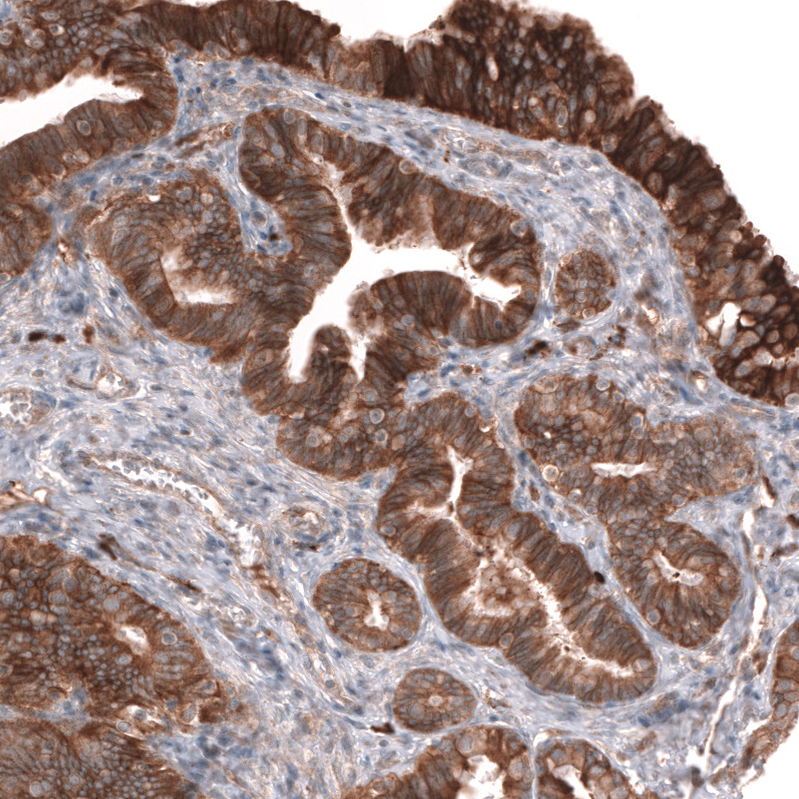

Immunohistochemistry analysis in human prostate and skeletal muscle tissues using AMAb91898 antibody. Corresponding ADAM10 RNA-seq data are presented for the same tissues.